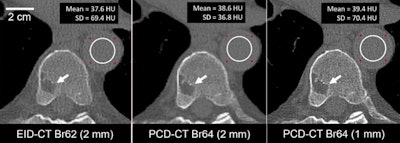

Photon-counting-detector CT systems measure individual x-ray photons as they pass through a patient's body, rather than the conventional CT approach, which measures the total energy of many x-rays at one time. The technology offers benefits compared with standard CT such as less noise during the exam, better spatial resolution, and reduced radiation dose, noted a group led by Kishore Rajendran, PhD, also of the Mayo Clinic.

McCollough's group found that the high-resolution mode of the photon-counting CT scanner showed 125-micron in-plane spatial resolution and 0.3-mm longitudinal resolution, "the smallest reported to date for a clinical CT system," the investigators wrote. It also produced a 66-ms temporal resolution multienergy imaging in dual-source mode, noise reduction of up to 47%, and dose reduction of up to 30% compared with conventional CT.